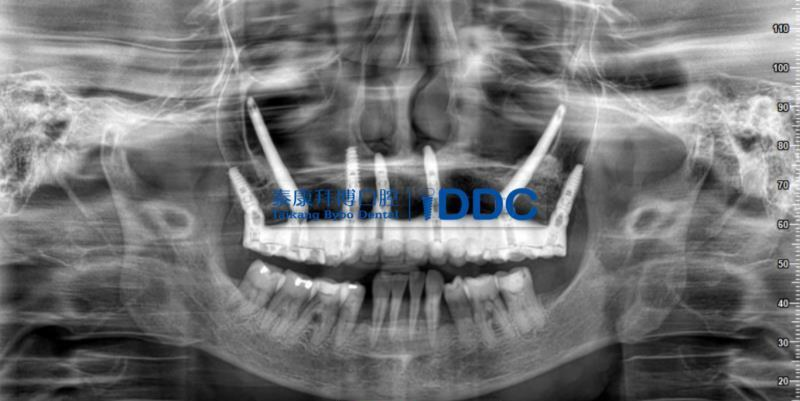

舒凌院长曾接治过一位上颌骨极度萎缩的患者。牙齿不好长期不能正常进食的林先生,健康状态受到了严重的影响,本就不好的肠胃功能负担更重,造成身体的营养吸收和骨质情况都很糟糕,这又反过来导致林先生口腔上颌骨骨质极度缺失,牙槽嵴严重萎缩,目前任何常规修复都非常不好处理。

普通种植无法进行,但任凭牙齿缺失的情况继续下去,林先生的身体健康水平就会继续下滑,更有可能诱发或加重多种疾病,严重危害全身健康。

眼看着牙齿的情况不能再拖下去了,林先生求诊到上海泰康拜博口腔医院,但因为家境困难,林先生一时难以拿出这么多的费用。病况急迫,种植院长舒凌仁心仁术,为客人垫付了部分材料费,让手术尽快进行。

在上海泰康拜博口腔医院 IDDC 疑难种植中心,舒院长经过术前严谨科学的设计,结合现代口腔的国际先进种植技术和顶尖种植材料,为林先生成功进行了上颌双侧颧种植体种植(穿颧)手术,以及下颌即刻种植手术。

术后,林先生未出现明显术后反应,没有明显肿胀、疼痛等不适症状。当天就戴上了全口固定临时牙桥,即刻就可以正常进软食。舒凌院长表示,临床工作中的成就感,更多的是切实帮到患者。